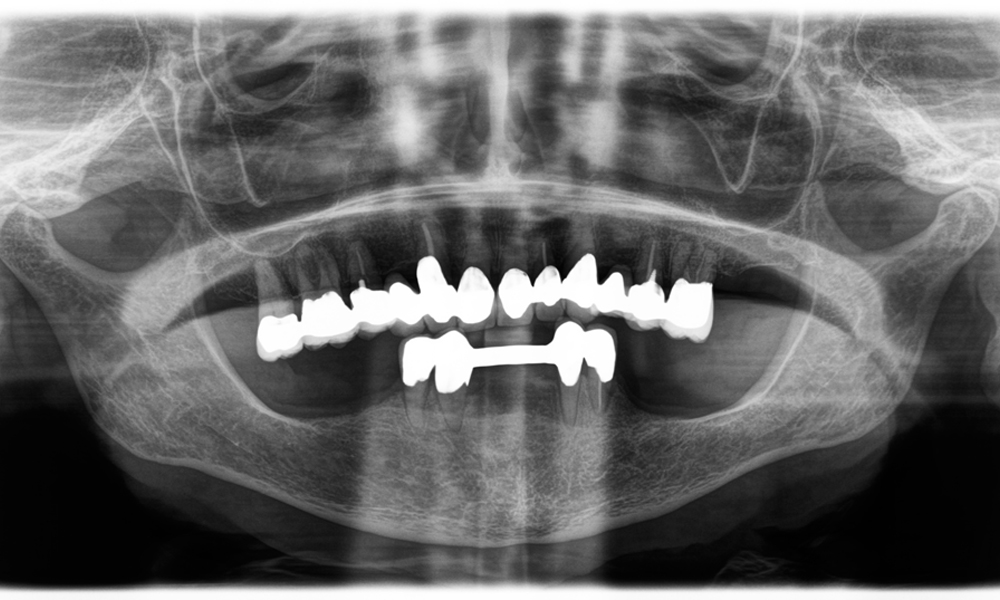

Ein weiteres Beispiel für die klinische Leistungsfähigkeit der Power Edition war der Austausch einer beschädigten Zirkonkrone bei einer 63-jährigen Patientin. Diese stellte sich aufgrund eines abgesplitterten Verblendungsteils ihrer 20 Jahre alten Zirkonkrone an Zahn 6 vor. Trotz der Position im Seitenzahnbereich empfand die Patientin dies als störend und wünschte eine neue Krone.

Die Power Edition ermöglichte eine präzise Schnittführung, wobei das erhöhte Drehmoment und die verbesserte Kühlung dazu beigetragen haben, die Krone ohne größeren Materialverlust zu entfernen. Das Spannsystem und das verbesserte Drehmoment erwiesen sich hierbei als essenziell.

Ein Röntgenbild, das Zähne und eine Zirkonkrone zeigt, vor schwarzem Hintergrund.

Abbildung 2: Austausch einer beschädigten Zirkonkrone: Präzise Erneuerung einer beschädigten Zirkonkrone an Zahn 6 mit minimalem Materialverlust.